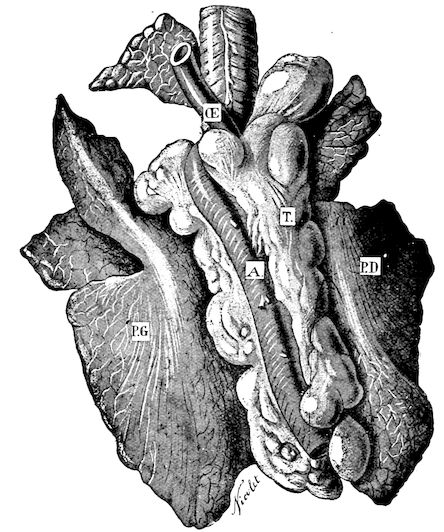

Fig. 1.—Rachitis in a young goat.

Rachitis is a disease of youth, and is common both to the human species and to all domestic animals. It is characterised by irregularities in development and by imperfect consolidation of the bones. The boundary between rachitis and osseous cachexia is difficult to define and in fact at the present moment the two diseases can scarcely be defined with exactitude. Rachitis again is often complicated with softening of the bones, disease of the limbs, arrested development, etc., but it must not be forgotten that although the irregularities in ossification and development of the skeleton are the symptoms most striking to the eye, they do not stand alone, and that from the point of view of development all the tissues, including the muscles, are more or less affected and that most of the physiological functions such as digestion and the secretion of urine are deranged.

Symptoms. The onset is absolutely insidious and the diagnosis of rachitis is never made until nutrition has long been abnormal.

This disturbance of nutrition is revealed by irregularity and abnormality in appetite, by difficulty in rising and moving about, and by the animals lying down for long periods. The subjects are feeble, sluggish and badly developed.

Next supervenes the second phase characterised by deformity of bones. This is of two kinds—deformity in the neighbourhood of joints (deformity or enlargement of the epiphyses) and deformity of the diaphyses. The former results from irregularity in ossification of the articular cartilages. The latter is followed by loss of rigidity in the bones of the limbs which, under the influence of the body weight and of muscular contraction, bend in different directions.

The bones appear of increased thickness principally towards the 6articulations. The latter are deformed, and on palpation are found to be surrounded by uneven and irregular growths.

The front limbs are distorted. In young pigs, lambs, and less frequently in foals, calves and dogs, the jaws become deformed, and mastication is rendered difficult.

The vertebral column may also be affected, and lordosis (bending downwards of the back) or skoliosis (lateral bending of the back) is somewhat frequent.

Cyphosis, or upward bending of the back, seldom occurs, and when seen, sometimes results from disease other than rachitis.

General development is always interfered with and the young creatures are generally dwarfed.

The digestive apparatus is disordered, the appetite is irregular and sometimes depraved, while indigestion, gastritis, and enteritis are not exceptional. Physiological and pathological research has shown that the quantity of phosphoric acid eliminated in twenty-four hours in a rachitic child is double the quantity passed by a healthy infant. The amount of urea in the urine (which is a criterion of nutrition, and usually varies in proportion to the amount of food ingested) is, on the contrary, diminished even when highly nitrogenous food is given, thus suggesting diminution in nutrition.

Lesions. The lesions are represented by abnormal and irregular thickening around the interarticular cartilages. The cartilage is thickened, compressible, very spongy and without regular ossification. Diffused periostitis exists principally towards the extremities of the bone. Beneath the periosteum the surface of the bone appears rough and softened. On section the medullary canals are seen to be enlarged and filled with marrow of a gelatinous character. The Haversian canals are dilated, and the entire tissue appears very vascular. Chemical analysis proves that the mineral constituents of the bone, particularly the phosphates, have diminished by one-half; the organic constituents on the other hand are increased in a similar ratio, but the ossein is abnormal. Ossification has, in a word, been incomplete.